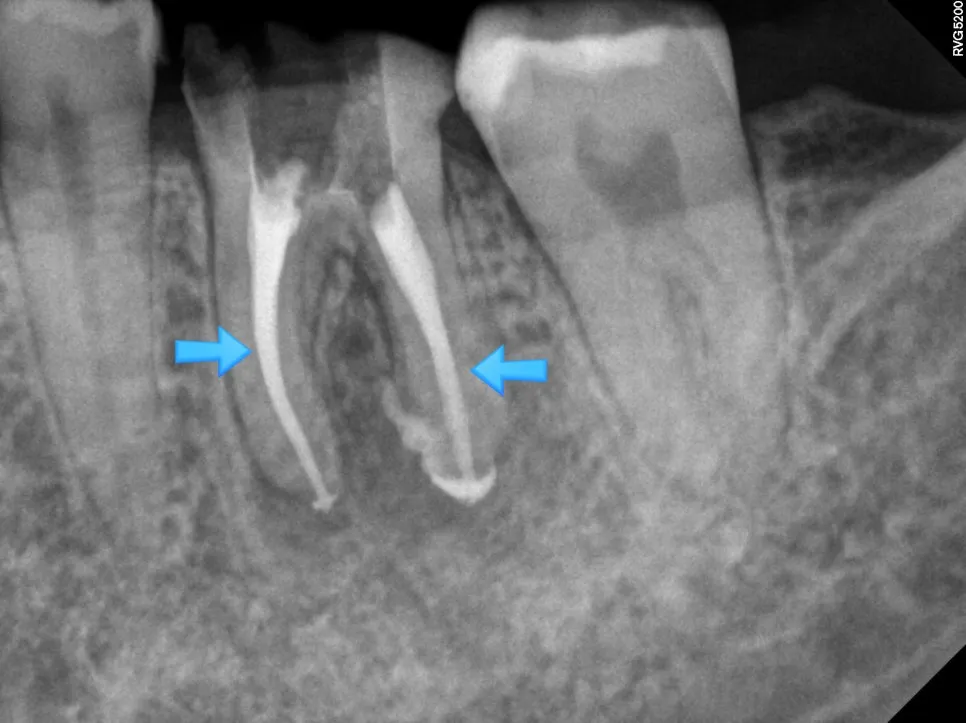

충분한 소독 후, 신경관 내부가 깨끗해졌다고 판단되면 생체 친화적인 재료로 빈틈없이 채워 넣습니다. 엑스레이상 하얗게 채워진 모습이 확인되면 신경치료 단계는 성공입니다.